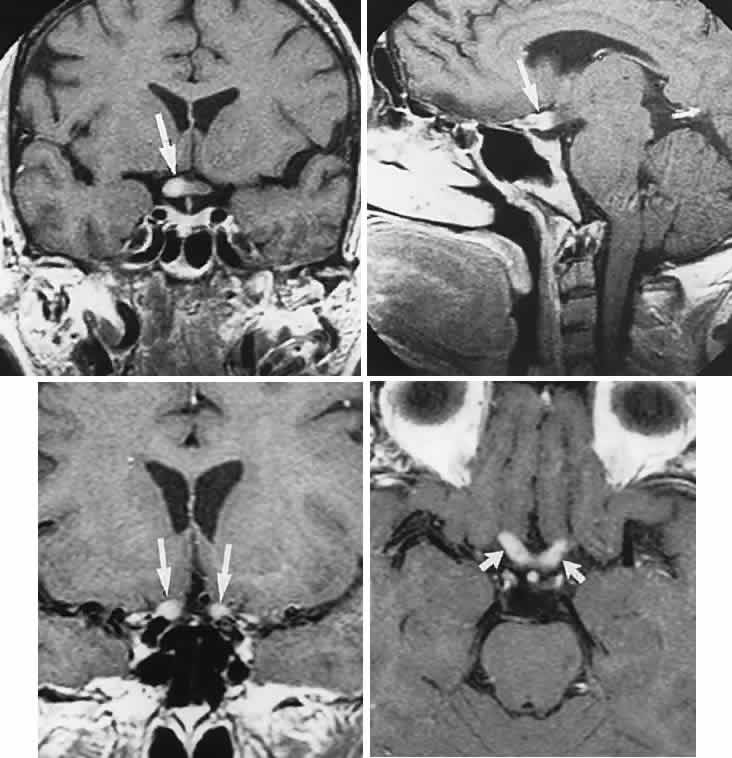

Back to Top